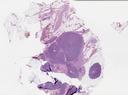

病理切片

SLIDE